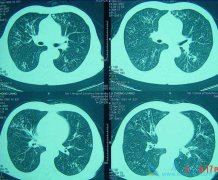

转移肺转癌是指的什么意思?移性肺癌症状有哪些症状?

转移性肺癌的意思就是在患者体内的任何位置的恶性肿瘤都是通过各种方式转移到患者的肺部。大约有60%的恶性肿瘤在初次检查时就有肿瘤转移,其中30%~50%肿瘤转移到肺部。像不同的肿瘤转移到肺部的发生率不同,其中,甲状腺癌、乳腺癌、肾癌、绒毛膜癌、骨 ...